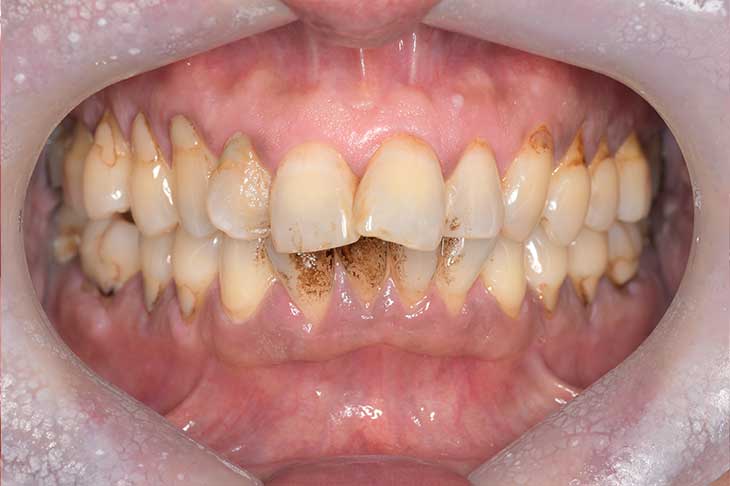

現在の治療費と異なる場合がございます。最新の治療費は料金表をご確認ください。CASE 1

Before

After

基本情報

| 主訴 | 見た目をきれいにしたい |

| 治療期間 | 6ヶ月 |

| 治療費 | ジルコニアボンド(セラミックの被せもの)¥165,000×7(税込み) オフィスホワイトニング4回 ¥4,400×4(税込み) ホームホワイトニング¥11,000 |

| リスク・副作用 | かみ合わせがとても強い方の場合、稀に割れてしまうことがあります。 |

| 先生からの提案 | 上の前歯6本と右下の2番目の歯はセラミックの被せもので治療。 残りの下の前歯5本はプラスチックの材料で虫歯を治療し、 ホワイトニングをおこないました。白くなったご自身の歯の色に合わせてセラミックの 被せものを作成しています。 模型上で完成後をシュミレーションし、上の歯茎の位置をきれいに見えるように 揃えています。(外科処置はしていません) |